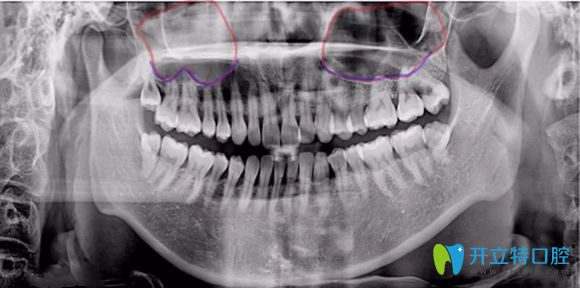

簡(jiǎn)單來說,上頜竇提升術(shù)是由于患者上頜骨高度不足,使種植體不能有效埋入,固位不行,就需要增加上頜骨高度而產(chǎn)生的手術(shù)。主要分兩種方式及內(nèi)提升和外提升。

內(nèi)提升它是指不用做額外切口,就在種植體窩洞處,用敲擊法,或者是超聲骨刀磨除上頜竇底的骨質(zhì),使上頜竇底提升。同時(shí)植入骨粉,使牙槽骨的高度也增加,這樣就能使種植體可植入的長(zhǎng)度增加,內(nèi)提升創(chuàng)傷較小,是臨床常用的方法。

外提升它適用于上頜骨高度極度不足,一般少于4mm,該情況下,可從上頜竇外側(cè)壁的骨板開窗打開上頜竇,剝離上頜竇底粘膜,植入骨粉來達(dá)到增加種植區(qū)域骨高度的術(shù)式。